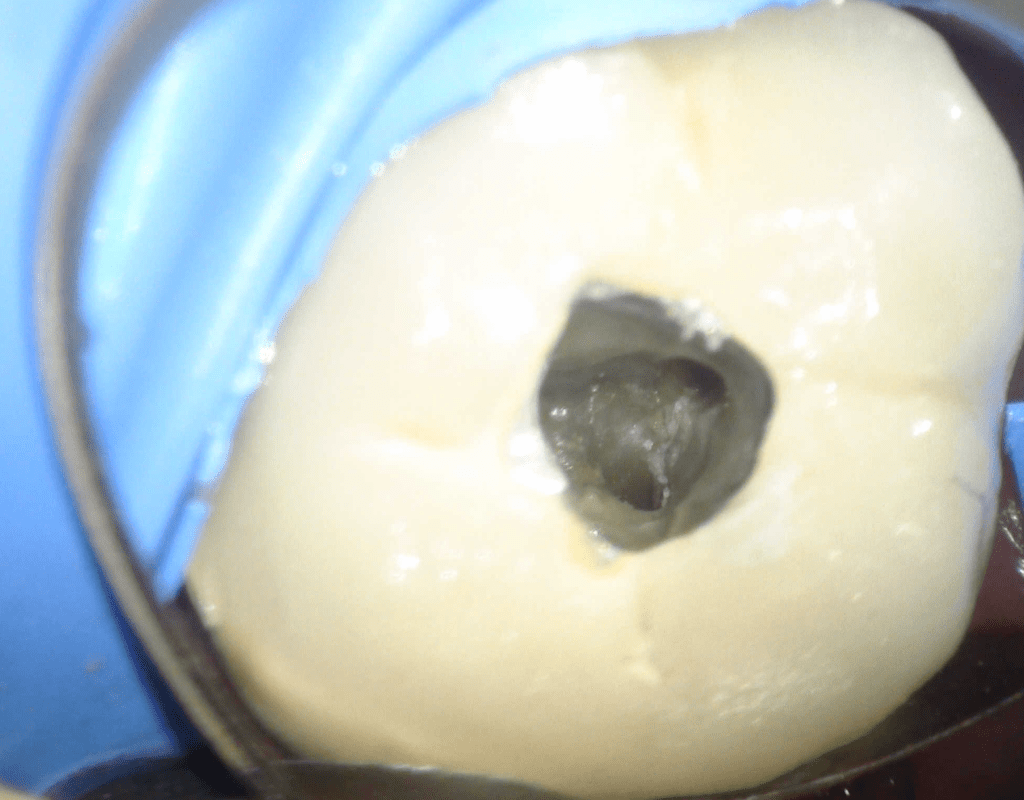

Diagnóstico de fisuras y fracturas

Fisura, remoción amalgama para explorar

Acceso ultraconservador a través de incrustación reciente